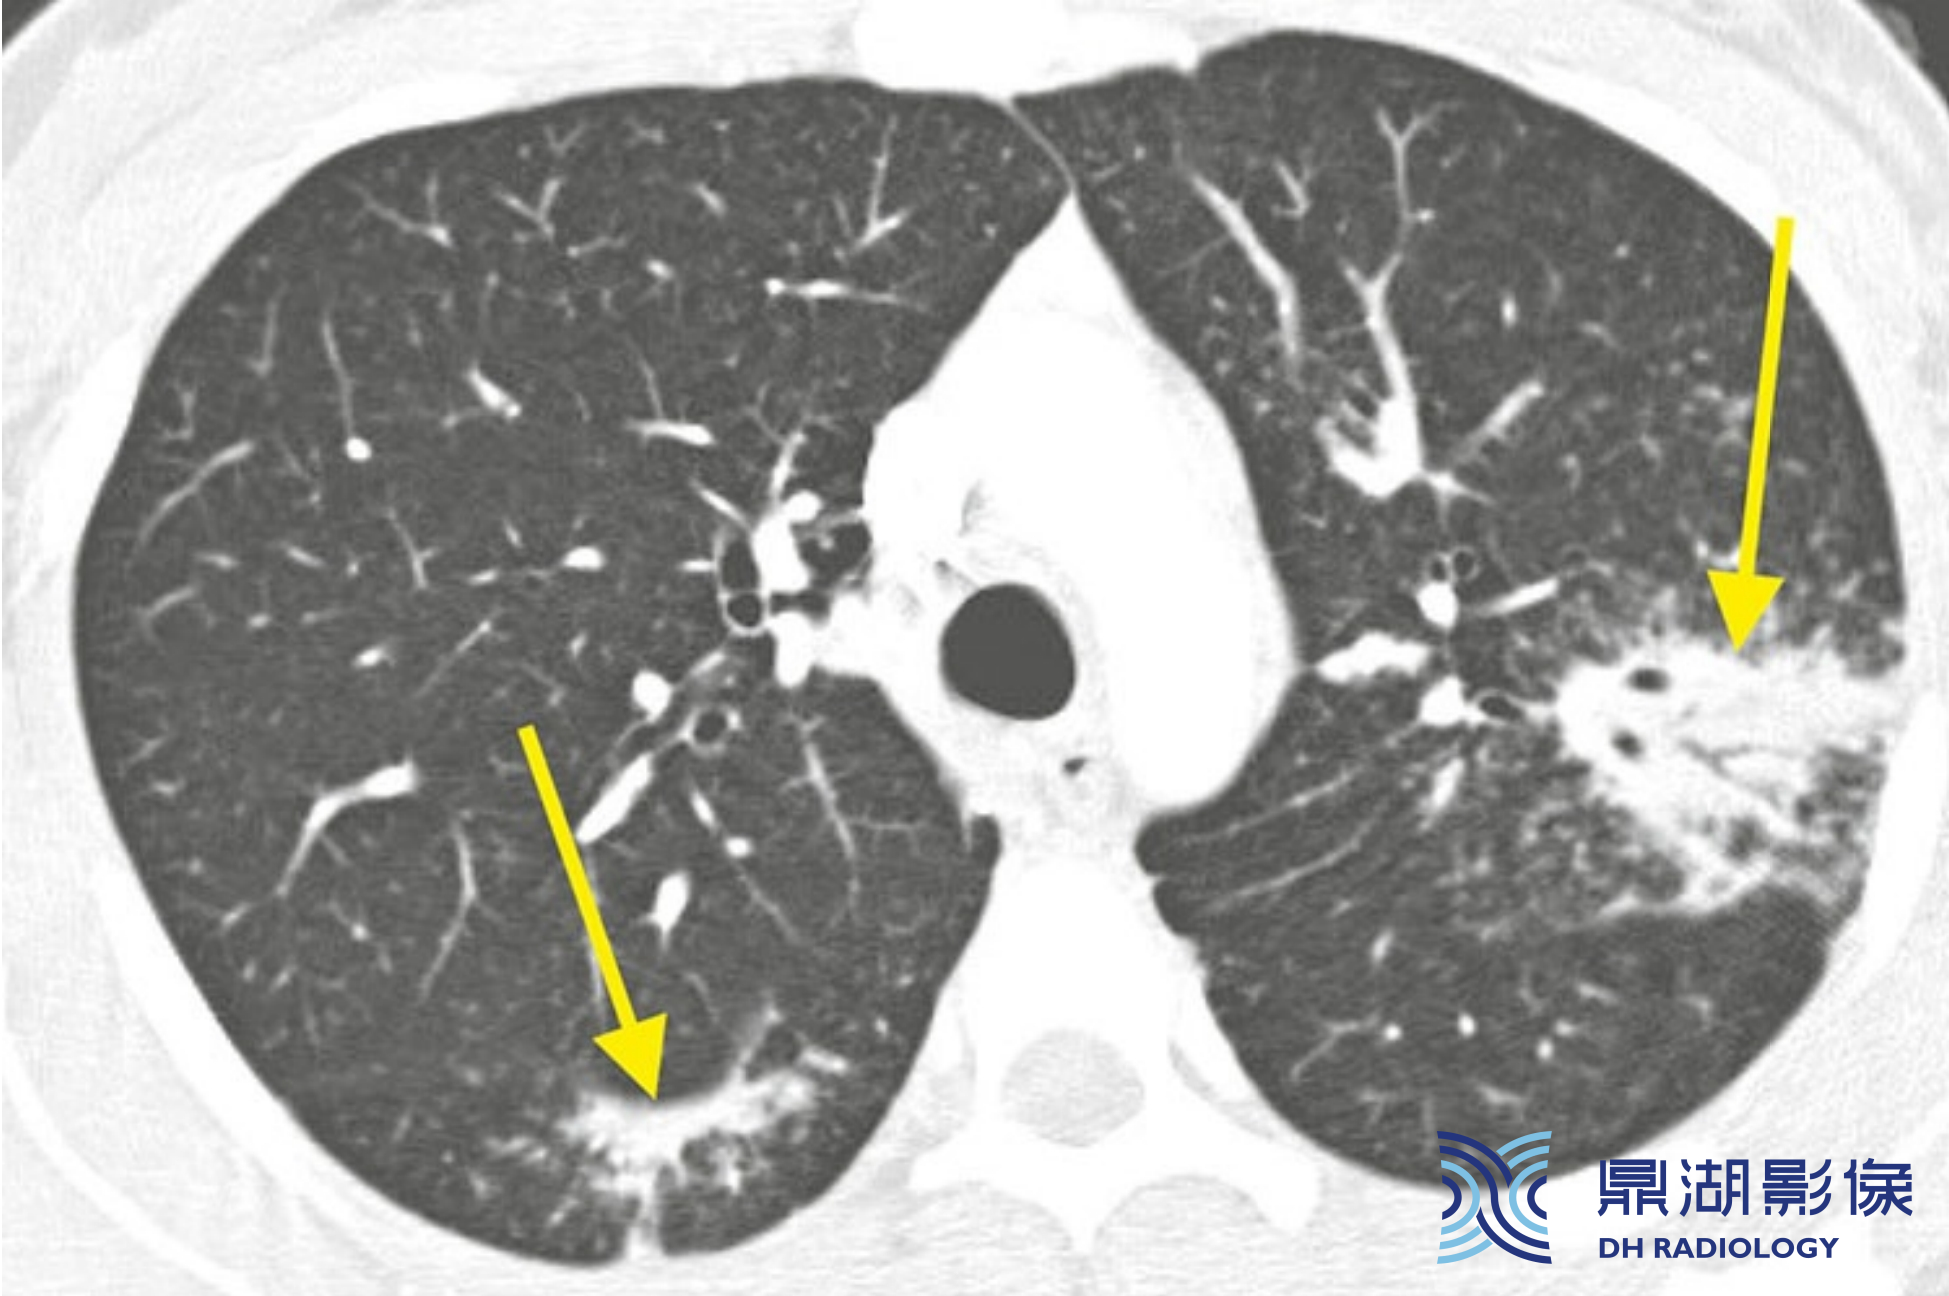

0bf39ca4c88272289348361260f5dc2c.png

肺泡型结节病及“星系征" 的典型表现。A和B支气管血管周围可见融合的肉芽肿所形成的肺门旁团块样实变。实变内可见支气管充气征。大片团块影周围分布的小结节即卫星结节,大团块影与其周围环绕的小结节合称为“ 星系征”

09bcb3e8a2a27fe3ab06e3875d3923b3.png

结节病伴实变。结节病可见实变(黄箭),伴有支气管血管周围(红箭)和胸膜下(蓝箭)散在分布的多发结节。实变代表融合的肉芽肿。

b9365aaf5ed567bd54c68adcd5629fa0.png

结节病伴实变。邻近支气管和叶间裂可见散在的实变(黄箭)。左肺上叶病灶内可见支气管充气征。实变区边缘可见小结节(卫星结节) ,此特征称为“星系征”,有助于区别结节病与其他病因所致的慢性肺实变。